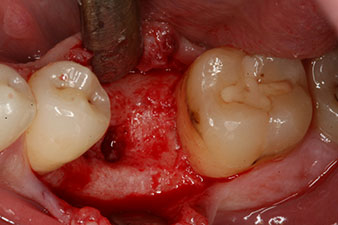

l’ossification de l’alvéole est incomplète

Fig. 2 : Six semaines plus tard, l’ossification de l’alvéole est incomplète dans la région de la racine mésiale.

Cependant, six semaines après l’extraction on observe une ossification incomplète après la préparation du lambeau mucopériosté dans la région de l’ancienne alvéole mésiale.

déficit osseux péri-implantaire

Fig. 5 : Le déficit osseux péri-implantaire doit être compensé par des fragments osseux autogènes afin de restaurer le contour des tissus péri-implantaires.

Ces valeurs auraient pu indiquer une cicatrisation ouverte, voire une restauration immédiate. Étant donné le volume osseux crestal insuffisant au niveau de l’implant, une augmentation osseuse a été pratiquée localement à l’aide des fragments osseux recueillis lors de la préparation du lit implantaire, et des points de suture effectués pour éviter le contact de la salive.